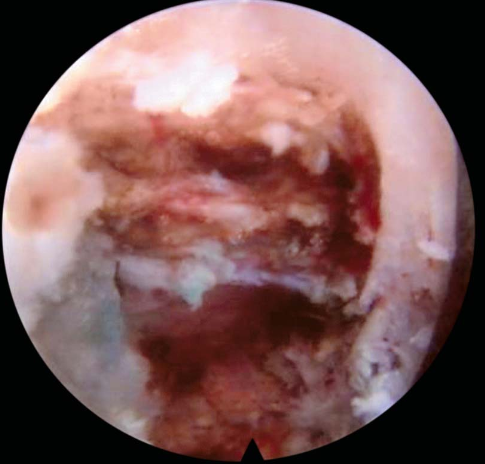

镜下完成标志:硬膜囊的波动及L5神经根减压游离,椎管内减压充分(图29)。

图29 镜下操作完成标志神经根漂浮试验阳性